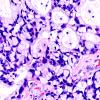

54A3 Metastasis, mucinous lung CA (Case 54) H&E 40X